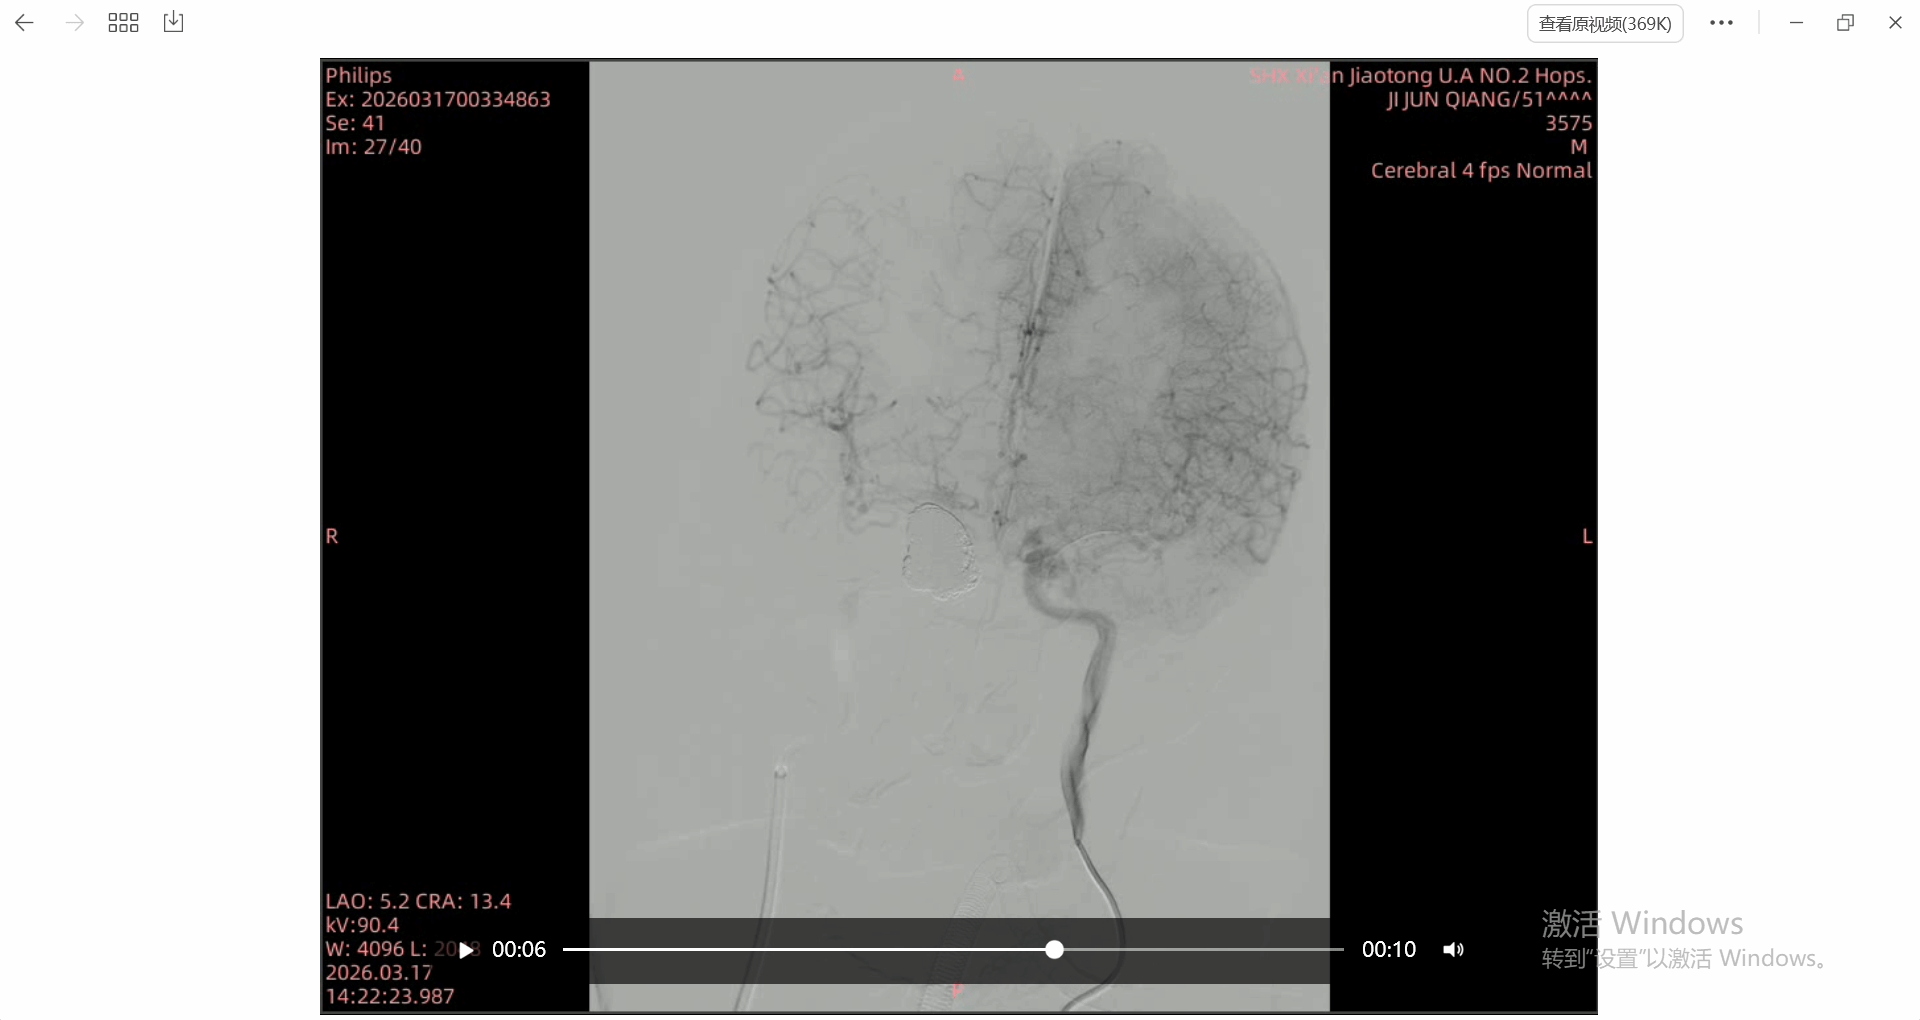

患者,50余岁男性,10年前因垂体瘤在外院行放射治疗,2周前因头痛在我院行颅脑MRA提示:右侧颈内动脉海绵窦段巨大异常流空影,考虑动脉瘤可能。入院后完善DSA提示:右侧颈内动脉海绵窦段巨大动脉瘤,分为两个子囊,动脉瘤大小约为40×38mm,瘤体巨大部分突入海绵窦及蝶窦。患者血管异常迂曲,且载瘤动脉近端及瘤颈部狭窄。患者巨大动脉瘤,且是放疗后继发的,考虑为假性动脉瘤可能,手术指征明确,如不及时处理,患者假性动脉瘤一旦破裂,可造成致死性鼻出血,风险极大。

术后造影